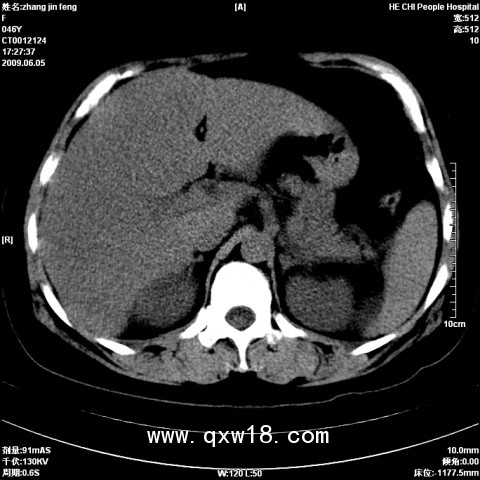

產(chǎn)品名:脂肪肝分析檢測(cè)診斷儀系統(tǒng)